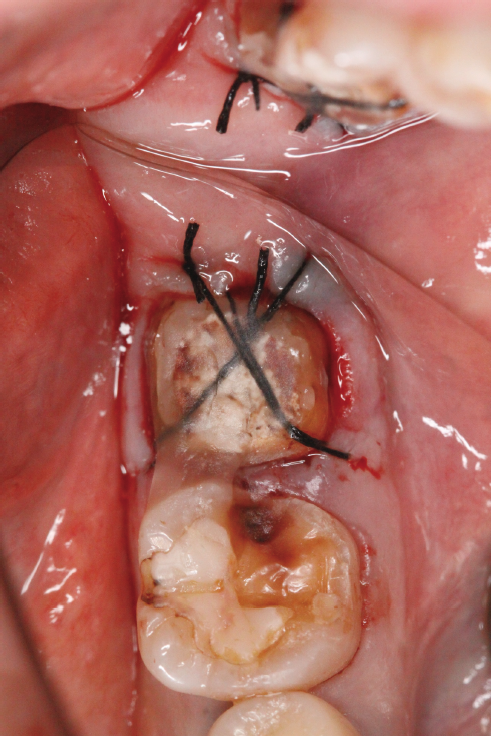

当院に来院される患者さんの多くは『他院で抜くしかないと言われる歯をなんとか残して欲しい』と言う希望の元来られます。現在歯を失う大きな原因となっている3大原因は『虫歯、歯周病、破折』です。多くは虫歯や破折なのですがこう言った歯の場合の治療には根管治療が必要になることがほとんどです。根管治療とは簡単に言うと、『ラバーダム』(写真1)と言われるゴムのカバーを歯に取り付け、根っこの中にある汚れを隅々まで取り、できる限り無菌に近い状態にして最後に蓋をする、と言う一連の流れになります。そしてその際に根っこの中にヒビが見つかったり根っこの中からのお掃除では綺麗になりきらず治癒しない場合は再植と言う治療になります。再植は『一回歯を抜いてお口の外でその歯を治療し再びお口の中に戻す』と言うものです。(写真2)『抜いた歯を再び植える』と言うことで再植と言う名がついています、他の方法で違う場所から歯を持ってきて(移動してきて)植える事を『移植』と呼んだりしてます。こちらの移植の方が臓器等、医科の分野でも使われる技術なので皆様には馴染みがあるかもしれませんね。